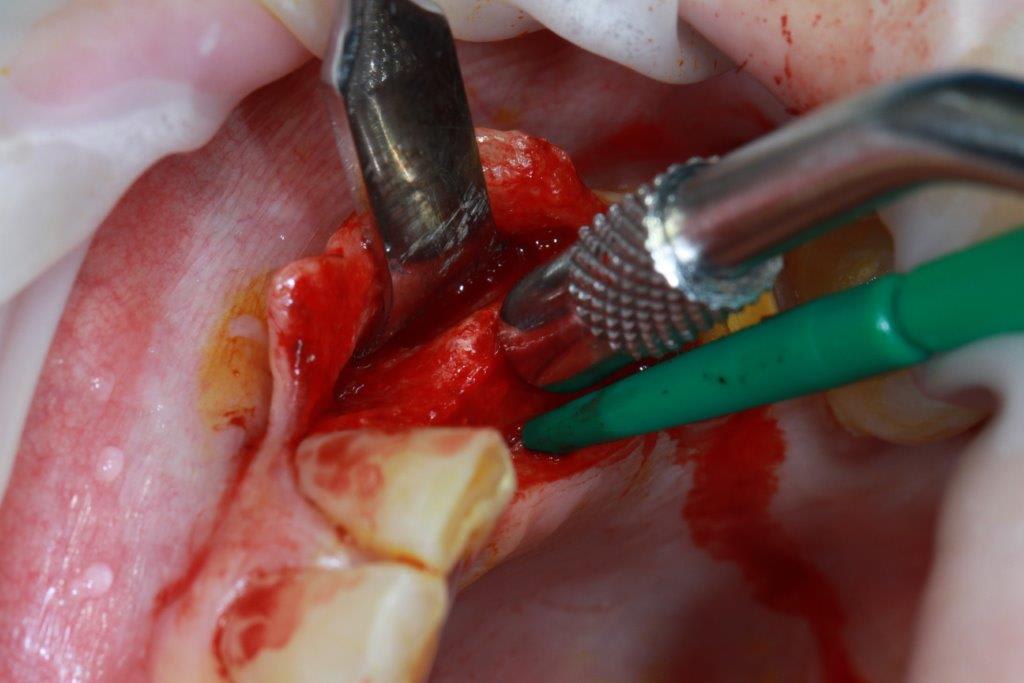

petit cas sympa ancien bridge très mobile....plutôt que d'extraire 25, j'ai déposé la couronne, retraité la dent stabilisation pendant deux mois puis séance d'ostéotension et ce jour pose de deux axioms PX 34120 après expansion...

Pas de preforage dans ce cas là, directement à l'osteotome demi lune

non, uniquement travail par voie crestale, très légère fêlure niveau 23, mais sans conséquence

comme je n'ai pas fait de décharges osseuse en vestibulaire, j'ai effectivement travaillé toute la longueur de la crête, mais, là j'ai ôtè les expanseurs avant de visser les implants car ce sont des PX qui ont un apex assez fin, pour des regular j'aurais pratiqué différemment.

en général (99,9% des cas) je ne constate aucune lyse osseusecrestale, ce type de chir. est très douce pour l'os, lame 15, et ostéotomes, pas de forage, pas de consommation d'os, pas d'agression ni de lavage (piezzo), et je fais toujours attention à laisser du sang (sauf pour les photos) ce qui est le meilleur pansement pour l'os.